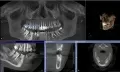

• Для того чтобы решить удалять или нет 16-й зуб, а также уточнить природу и размеры образования в области 37-го зуба необходимо сделать компьютерную томографию. Скорее всего, 16-й зуб надо будет удалить. 17-й зуб перелечить корневые каналы восстановить вкладкой и коронкой, в область 14-го и 16-го зубов поставить имплантат и провести синус-лифтинг. 22-й и 24-й зубы сделать при читать далее